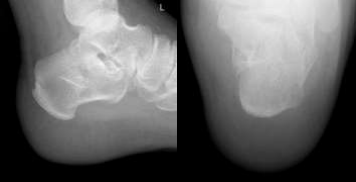

Postoperative Care and Optimizing Recovery and Monitoring Outcomes

Following the minimally invasive procedure, the patient's care focused on optimizing recovery and preventing potential complications. Thromboembolic prophylaxis with anticoagulants was resumed 12 hours postoperatively, Patient did not require much pain control and he was discharged home on the first postoperative day. Strict non-weight bearing on the left lower limb was enforced for the initial two weeks to allow for undisturbed fracture healing and soft tissue recovery. Regular follow-up appointments were scheduled within the orthopedic foot and ankle clinic to monitor progress and address any emerging concerns. Thromboembolic prophylaxis with Enoxaparin (40 mg once daily subcutaneously) was continued for two weeks following discharge. The dressing clinic visit within the first week confirmed no signs of infection or complications. Suture removal was performed at the two-week mark, revealing a well-healed wound with no soft tissue issues. After the initial non-weight bearing period, the patient progressed to partial weight bearing for gradual return to mobility. Follow-up radiographs (Figures 15, 16, and 17) were obtained to assess fracture alignment and stability. Additionally, a CT scan was performed within three weeks postoperatively (Figures 18, 19, 20, and 21) for in-depth evaluation of the internal components and fracture healing process. The crucial angle of Gissane on the follow-up CT scan measured approximately 145 degrees (Figure 22), indicating near-anatomical restoration of the posterior facet and a significant improvement from the initial measurements. Overall, the patient's postoperative course was uneventful, with no reported complications or concerns. Continued follow-up appointments and imaging at scheduled intervals will be crucial to monitor long-term fracture healing, maintain optimal outcomes, and address any potential issues that may arise.